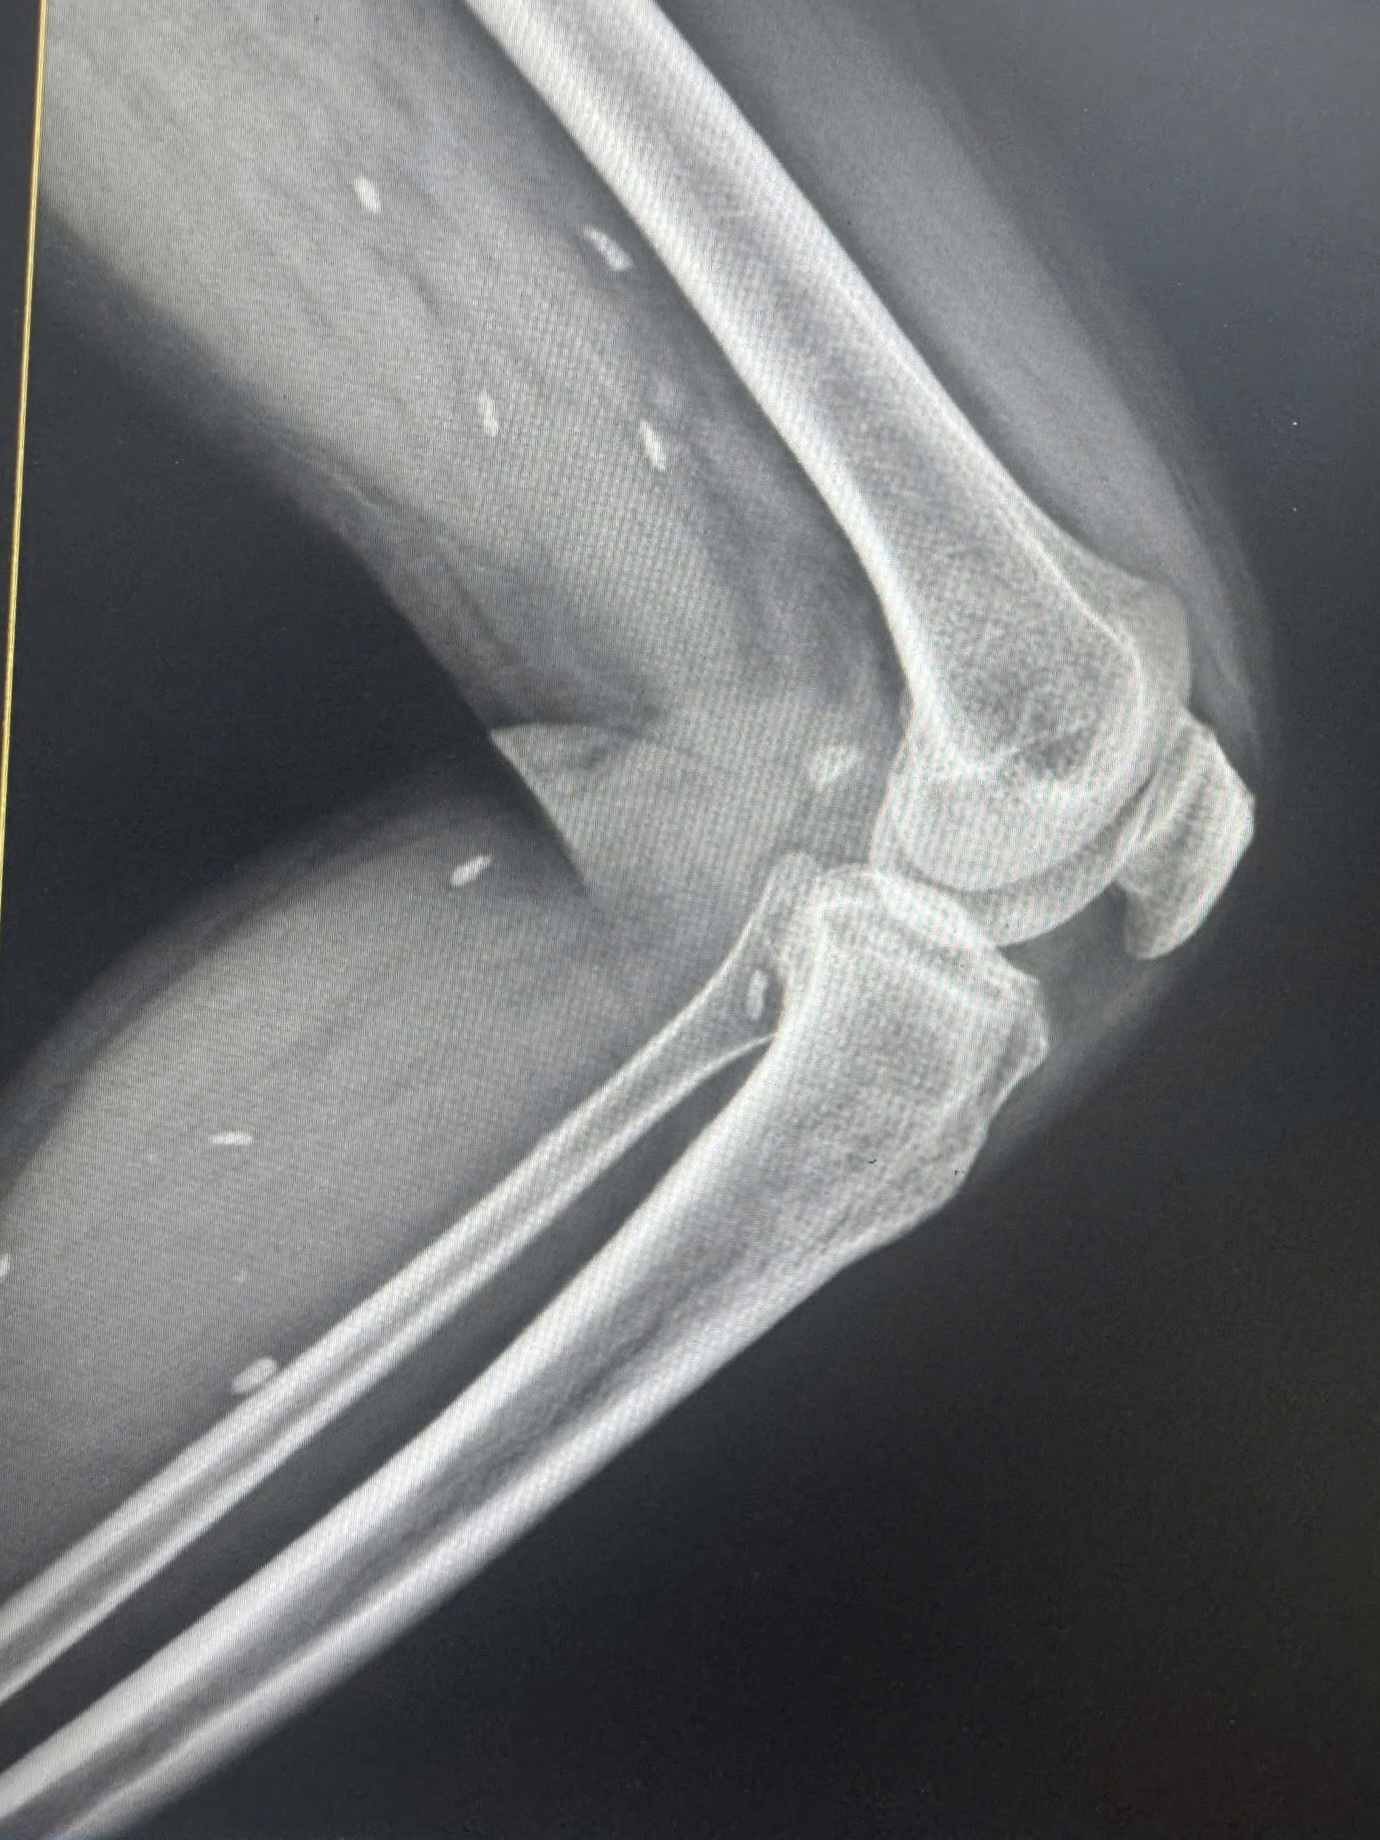

Nhiều kén sán kích thước như hạt gạo nằm rải rác ở các mô vùng xương đùi và cẳng chân bệnh nhân.

Người bệnh đến thăm khám khi có triệu chứng mệt mỏi, đau nhức nhiều ở vùng chân, lưng, hạn chế vận động… Bệnh nhân được chỉ định thực hiện chụp X- quang thường quy.

Bác sĩ Đỗ Hồng Thanh, Phó Giám đốc Trung tâm Y tế khu vực Thạch Hãn chia sẻ với Sức khỏe & Đời sống , kết quả X – quang phát hiện nhiều kén sán kích thước như hạt gạo nằm rải rác ở các mô vùng xương đùi và cẳng chân bệnh nhân.